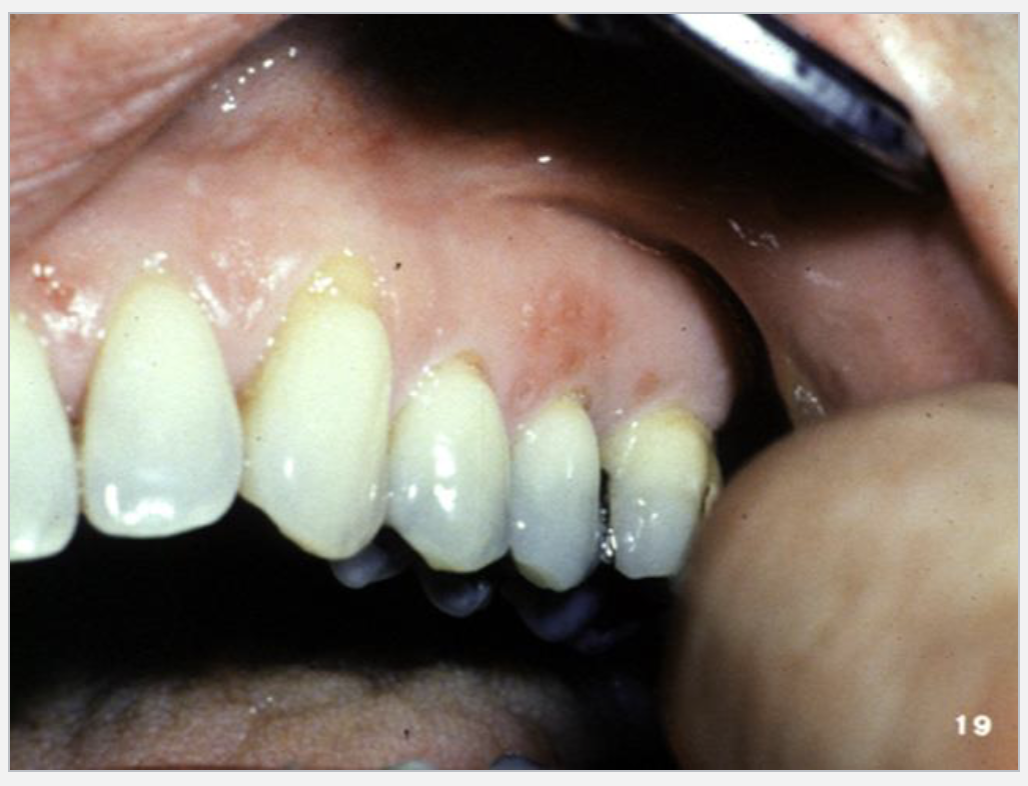

2

Q

What’s this?

A

RECURRENT APHTHOUS STOMATITIS